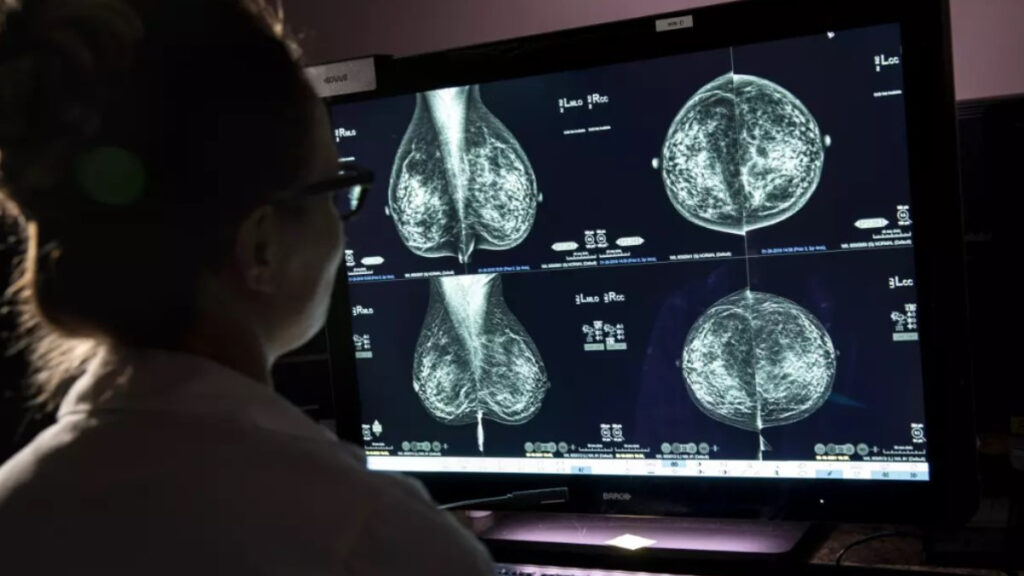

Cáncer de mama: la importancia de las mamografías

- La mamografía es una herramienta fundamental para la detección temprana del cáncer de mama porque permite identificar tumores o anomalías antes de que aparezcan síntomas visibles.

- Es un estudio rápido, no invasivo y accesible, con campañas gratuitas o de bajo costo disponibles en muchos sistemas de salud pública.